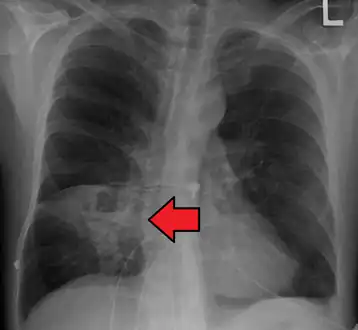

Pulmonary abscess on CXR

Pulmonary abscess on CXR -